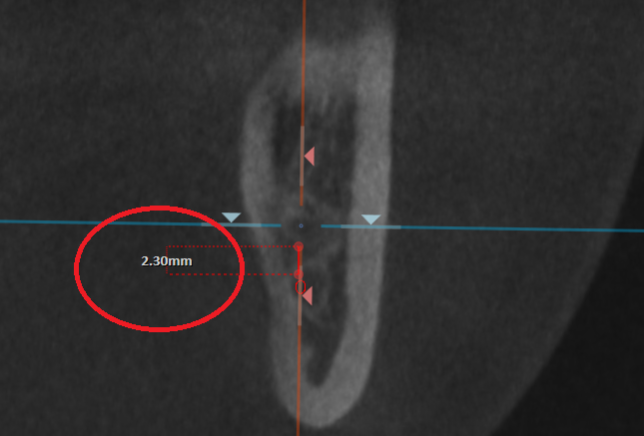

CTの角度を変えて、親知らずと下顎管の距離を計測します。

その距離、およそ2.3mm

ここまで下顎管との距離が近いと、親知らずを抜く際に、神経や動脈を損傷するリスクがあります。

神経を損傷すれば、麻痺が残る可能性がありますし、

動脈を損傷すれば、大量出血の可能性があります。